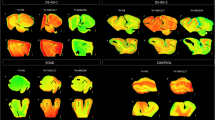

Phosphor-screen autoradiography was performed on brain tissue slides containing the three regions of interest: EC, STS and VC. Strong and selective [F-18]-AV-1451 binding was detected in all tangle-containing regions matching precisely the observed pattern of PHF-tau immunostaining corresponding to the different Braak stages (Fig. 1). Individuals in the low Braak category (stages I–II) (Fig. 1a) showed [F-18]-AV-1451 binding exclusively in EC; intermediate Braak cases (stages III–IV) (Fig. 1b) exhibited tracer binding in EC and STS; and high Braak cases (stages V–VI) (Fig. 1c) showed binding in all three ROIs. Of note, binding was almost completely blocked after incubating the slides with 1 μM unlabeled AV-1451, demonstrating the specificity of the signal. As expected, no signal was detected in the white matter or in non-tangle containing regions in any of the three slides examined. Consistent with our previously reported observations [14], the distribution of the autoradiographic [F-18]-AV-1451 binding closely mirrored the pattern of PHF-1 immunostaining reactivity on adjacent slices with the highest amount of signal being observed in cortical layers III and V, as expected based on the well-known robust density of tangle lesions in those cortical layers, as opposed to the more scattered plaque distribution pattern revealed by Aβ immunostaining (Fig. 1d). Our previous studies using a fine grain nuclear photographic emulsion and immunohistochemistry to obtain resolution at the cellular level, demonstrated that [F-18]-AV-1451 selectively binds to PHF-tau containing lesions, including NFTs (intra and extraneuronal) and PHF-tau containing neurites, but does not bind to Aβ plaques or amyloid-laden vessels [14].

Microphotographs of postmortem brain tissue sections depicting Aβ and PHF-1 tau immunostaining, [F-18]-AV-1451 phosphor-screen autoradiography and blocking conditions in adjacent slides from representative subjects at different Braak stages [2]: a low Braak, b intermediate Braak, and c high Braak, and high magnification microphotographs depicting Aβ and PHF-1 tau immunostaining and [F-18]-AV-1451 phosphor-screen autoradiography of the STS from case #21 (d). [F-18]-AV-1451 binding was detected in all tangle-containing regions matching the pattern of PHF-tau immunostaining across the different Braak stages, but not the Aβ immunosignal. No [F-18]-AV-1451 binding was detected in white matter or in cortical regions lacking NFTs. Scale bar 1 cm (a–c), 2 mm (d). Aβ β-amyloid, IHC immunohistochemistry, NFT neurofibrillary tangles, PHF paired helical filament

Taking advantage of the large collection of well-characterized legacy postmortem tissue samples in our MADRC Neuropathology Core, we selected a series of 22 brains from subjects representing the entire spectrum of Braak staging [2]. We selected blocks containing three brain regions (EC, the cortex lining the STS and the VC) to illustrate the progressive accumulation and predicted spreading of NFTs from transentorhinal/entorhinal cortices to limbic structures and isocortical areas. Our results from phosphor-screen autoradiography confirmed that [F-18]-AV-1451 avidly bound to PHF-tangle containing slices demonstrating very low nonspecific binding to the whiter matter. [F-18]-AV-1451 binding was confined to the EC in cases with low Braak stage (I–II) reflecting the presence of incidental age-related NTFs in these subjects, progressing to the STS in subjects with intermediate Braak stage (III–IV), and extending to the VC in subjects with high Braak stage (V–VI). In agreement with our previous observations [14], the laminar autoradiographic pattern of distribution of [F-18]-AV-1451 revealed a strong labeling in particular of layers III and V, matching the preferential laminar distribution of NFTs on adjacent immunostained sections. These data strongly suggest that [F-18]-AV-1451 is a very promising surrogate marker for estimating in vivo Braak staging; something that may prove to have important practical implications. As it has been recently suggested, knowledge of the in vivo Braak staging using tau PET imaging could be particularly valuable to stratify participants in clinical trials into more homogeneous groups, improving the power of the trial and reducing the required sample size [22]. It could also be useful in helping patients and caregivers understand the likely rate of disease progression over time and develop a plan of care.